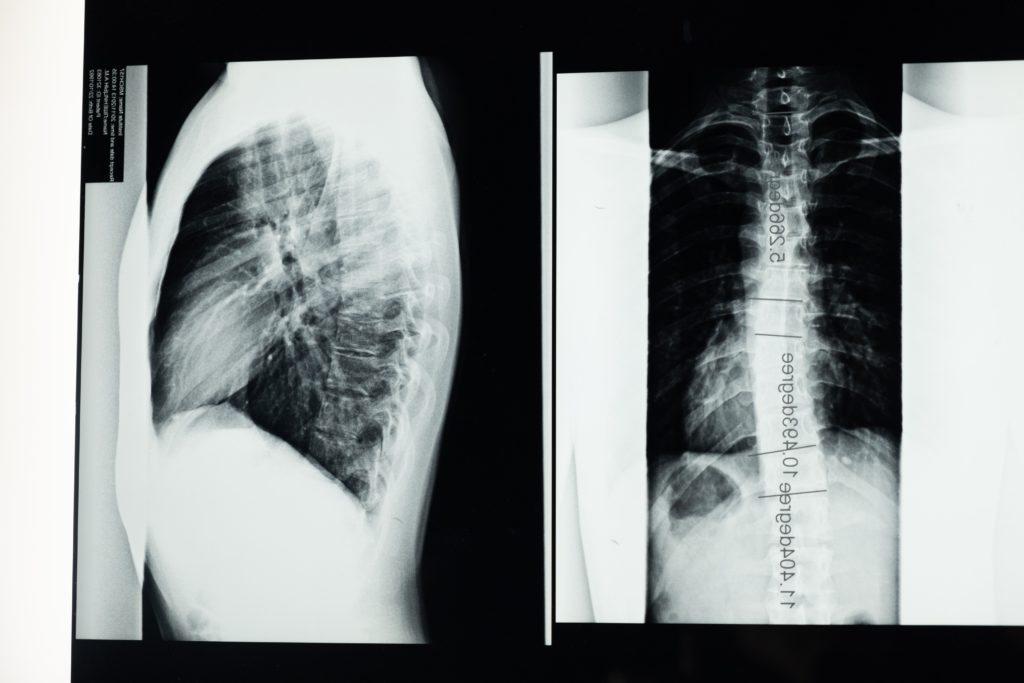

In questo articolo verrà approfondito il tema sempre attuale della scoliosi in chiave moderna, prendendo in considerazione la zona toracica e il suo contenuto e come esso cambia in una scoliosi.

Sarebbe ovvio pensare che, essendo la scoliosi una deformazione sui 3 piani di movimento (frontale, sagittale e trasversale), nel caso di una scoliosi toracica più o meno grave che quindi interessa anche la cassa toracica e le relative coste, vi sia un’influenza sulla funzionalità cardiaca e respiratoria. Ma sarà davvero così?